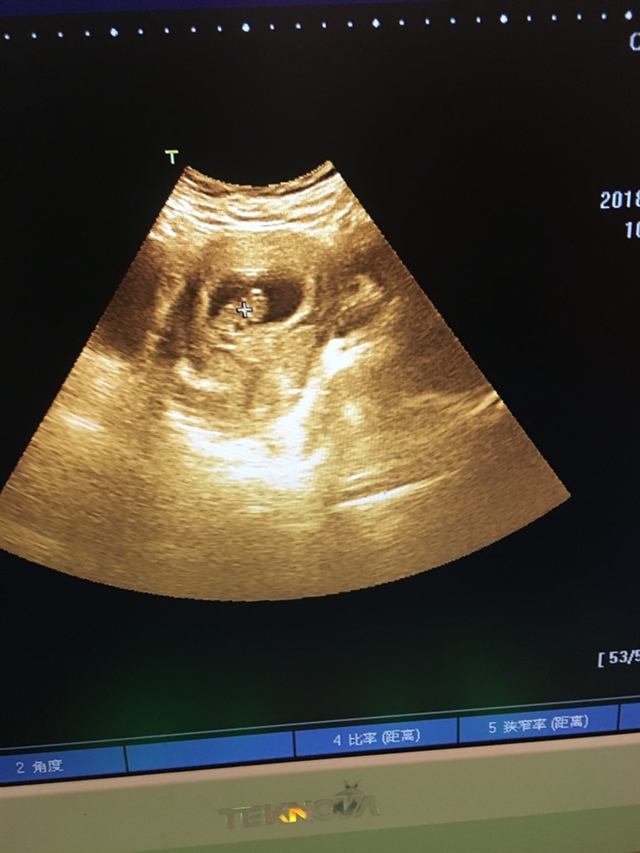

孕9周+5天

看到个可爱的宝宝。你这应该有11,12周了吧